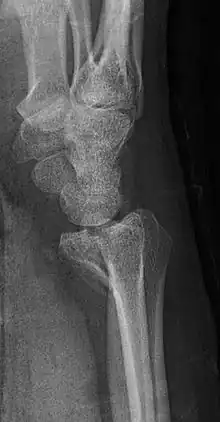

Barton's fracture

A Barton's fracture is a type of wrist injury where there is a broken bone associated with a dislocated bone in the wrist, typically occurring after falling on top of a bent wrist.[1] It is an intra-articular fracture of the distal radius with dislocation of the radiocarpal joint.[2]

There exist two types of Barton's fracture – dorsal[3] and palmar, the latter being more common. The Barton's fracture is caused by a fall on an extended and pronated wrist increasing carpal compression force on the dorsal rim. Intra-articular component distinguishes this fracture from a Smith's or a Colles' fracture. Treatment of this fracture is usually done by open reduction and internal fixation with a plate and screws, but occasionally the fracture can be treated conservatively.[4]